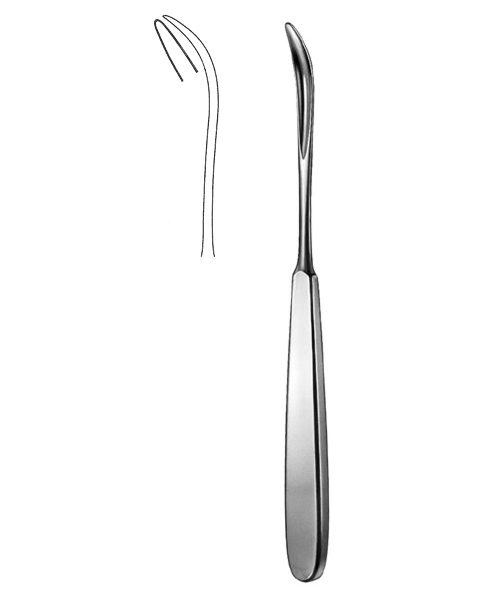

- Surgical Instruments, Suture

Ligature Catcher

- Size : 22 CM - 8 3/4"